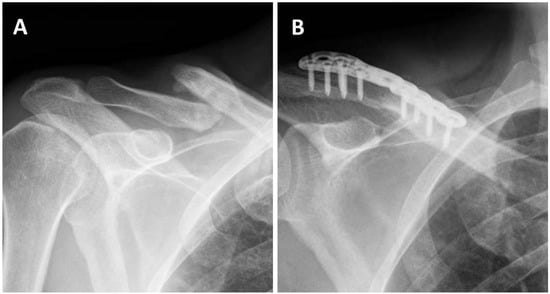

Addition of Bone Marrow Aspirate Concentrate Resulted in High Rate of Healing and Good Functional Outcomes in the Treatment of Clavicle Fracture Nonunion: A Retrospective Case Series

3. Results